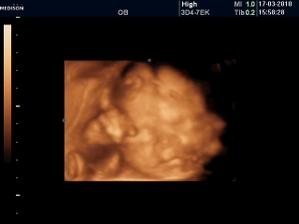

Vyrobene z velkej lasky

diky lutsine. no vobec nebolo vidno....ale uz mi je tazsie brusko ted to tak pocitujem ze ledva sa obujem.